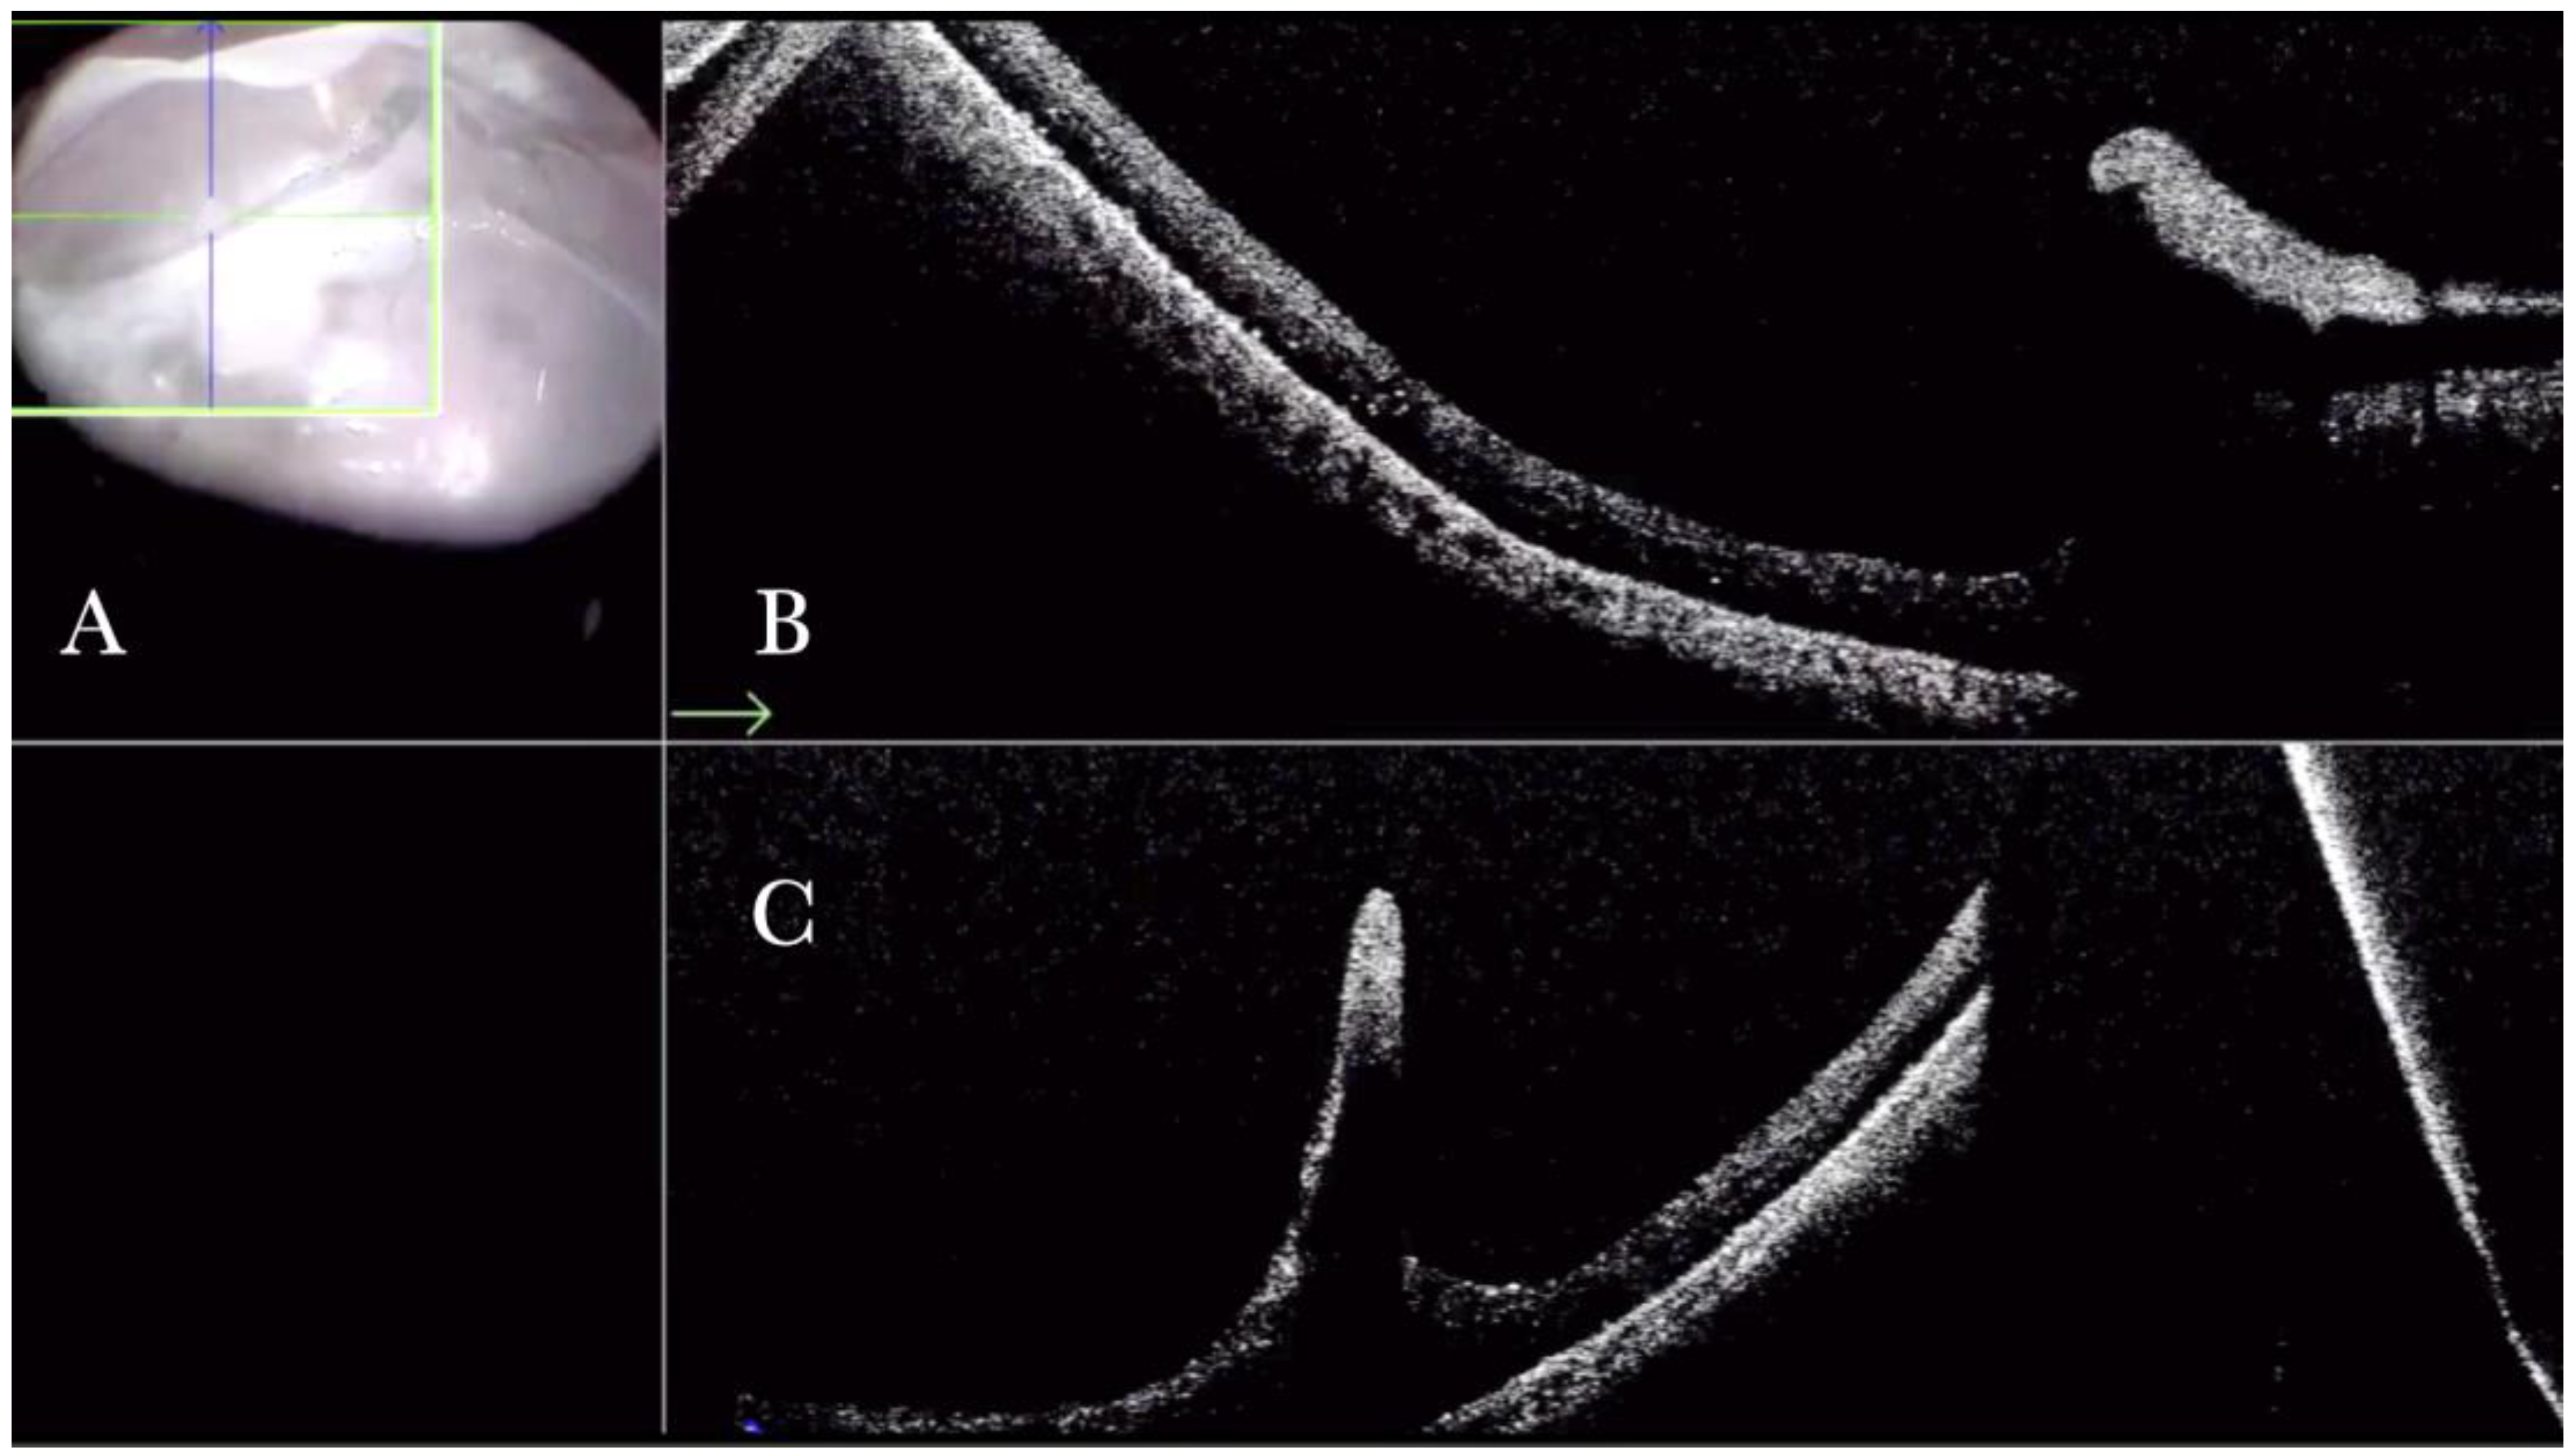

Figure 12.

(A) Microscope view of the macular area in case of myopic traction maculopathy in stage 4C (macular detachment with full-thickness macular hole (FTMH)) after implanting a macular buckle and peeling the inner limiting membrane (ILM) creating an ILM flap. The transillumination of a fiber optic inserted into the buckle allows us to guess the location of the buckle itself. The FTMH is not visible under the air. (The green box indicates the field-of-view of the OCT scan, the green and blue lines within the green box show the vertical and horizontal scan planes). (B) The intraoperative optical coherence tomography (i-OCT) B horizontal (green arrow) scan shows, very clearly, the indentation of the macula from the scleral side due to the presence of a macular buckle. (C) The i-OCT B vertical scan shows, very clearly, the indentation of the macula. The white arrow shows the FTMH, which is now well-positioned over the buckle, and the presence of the ILM flap even under the air.